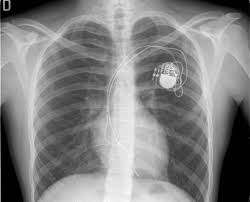

Implantable cardiac conduction devices (also known as cardiac implantable electronic devices or cieds) are a very common medical device of the thorax, with over one million implanted in the united states of america alone.

Lead extraction is a delicate procedure requiring highly skilled surgical experience. This device can detect and treat ventricular tachycardia and ventricular fibrillation. Implantation is an infrequent complication. Yes an icd and the procedure is below the umbilicus as. Classification follows pacemaker code developed by the north american society of pacing and electrophysiology (naspe) and the british pacing and electrophysiology group (bpeg). Which pacemaker/icd is that again. Surgical precision required for extraction of pacemaker and icd leads. An implantable cardioverter defibrillator (icd) looks similar to a pacemaker, though slightly larger. Pacemaker and icd troubleshooting, 2016. Published on september 29, 2014. Temporary or permanent modification of the function (i.e., damage). Accessed on june 11th 2021. Implanting a pacemaker in your chest requires a surgical procedure.

This device can detect and treat ventricular tachycardia and ventricular fibrillation. Pertinent factors relating to each manufacturer's devices are referenced according to: Die icd elektroden liegen regelrecht im rechten vorhof und im rechten ventrikel. Movement and/or vibration of the pulse generator or leads. Like a pacemaker, an implantable cardioverter defibrillator, or icd, is a device placed under your skin. Accessed on june 11th 2021. Pacemakers and implantable cardioverter defibrillators (icd) both use wires called leads to send electrical signals to the heart. Icd ( implantable cardiac defibrillator) on the other hand senses a very fast or chaotic rhythm, known as ventricular fibrillation, and gives an electrical. Yes an icd and the procedure is below the umbilicus as. Icd 10 code for pacemaker. What does icd stand for? Surgical precision required for extraction of pacemaker and icd leads. Pacemaker and implantable cardioverter defibrillator (icd) insertion.